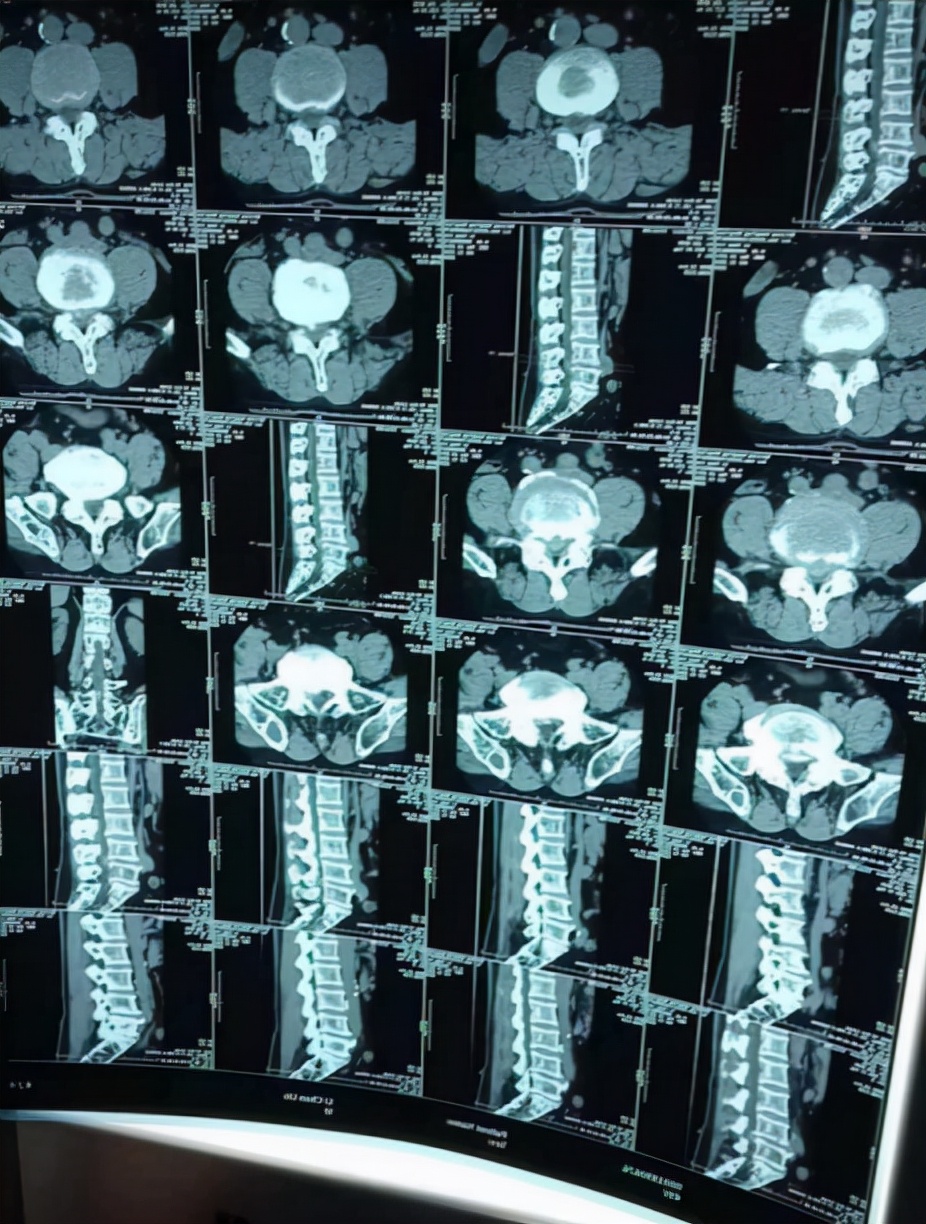

真实腰间盘突出伴椎管狭窄、骨质增生的微创病例分享:

该患者因腰部疼痛同时伴左下肢疼痛、麻木,活动受限1个月就诊。

【症状】:腰部疼痛、左下肢疼痛麻木,行动不便。

【诊断结果】:

1、腰3-5椎间盘突出伴椎管狭窄

2、骨质增生

【治疗方案】:低温等离子射频消融术

【术后】:术后在院观察三天,无不适后回家休养一周,目前恢复良好,疼痛、麻木感基本消失,行动自如。